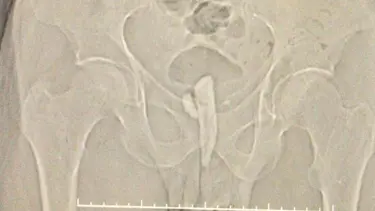

Üroloji Doktoru Metin Kılıç'ın yaptığı kontrolde, Köroğlu'nun idrar kanalı ve kesesinde bir cisim saptandı. 20 Ekim'de hastanede yaklaşık 2 saat süren operasyonla idrar kanalından keseye doğru uzanan 8 santim uzunluğundaki parça alındı. Çıkarılan cismin odun parçası olduğu ve etrafının taşlandığı belirlendi.